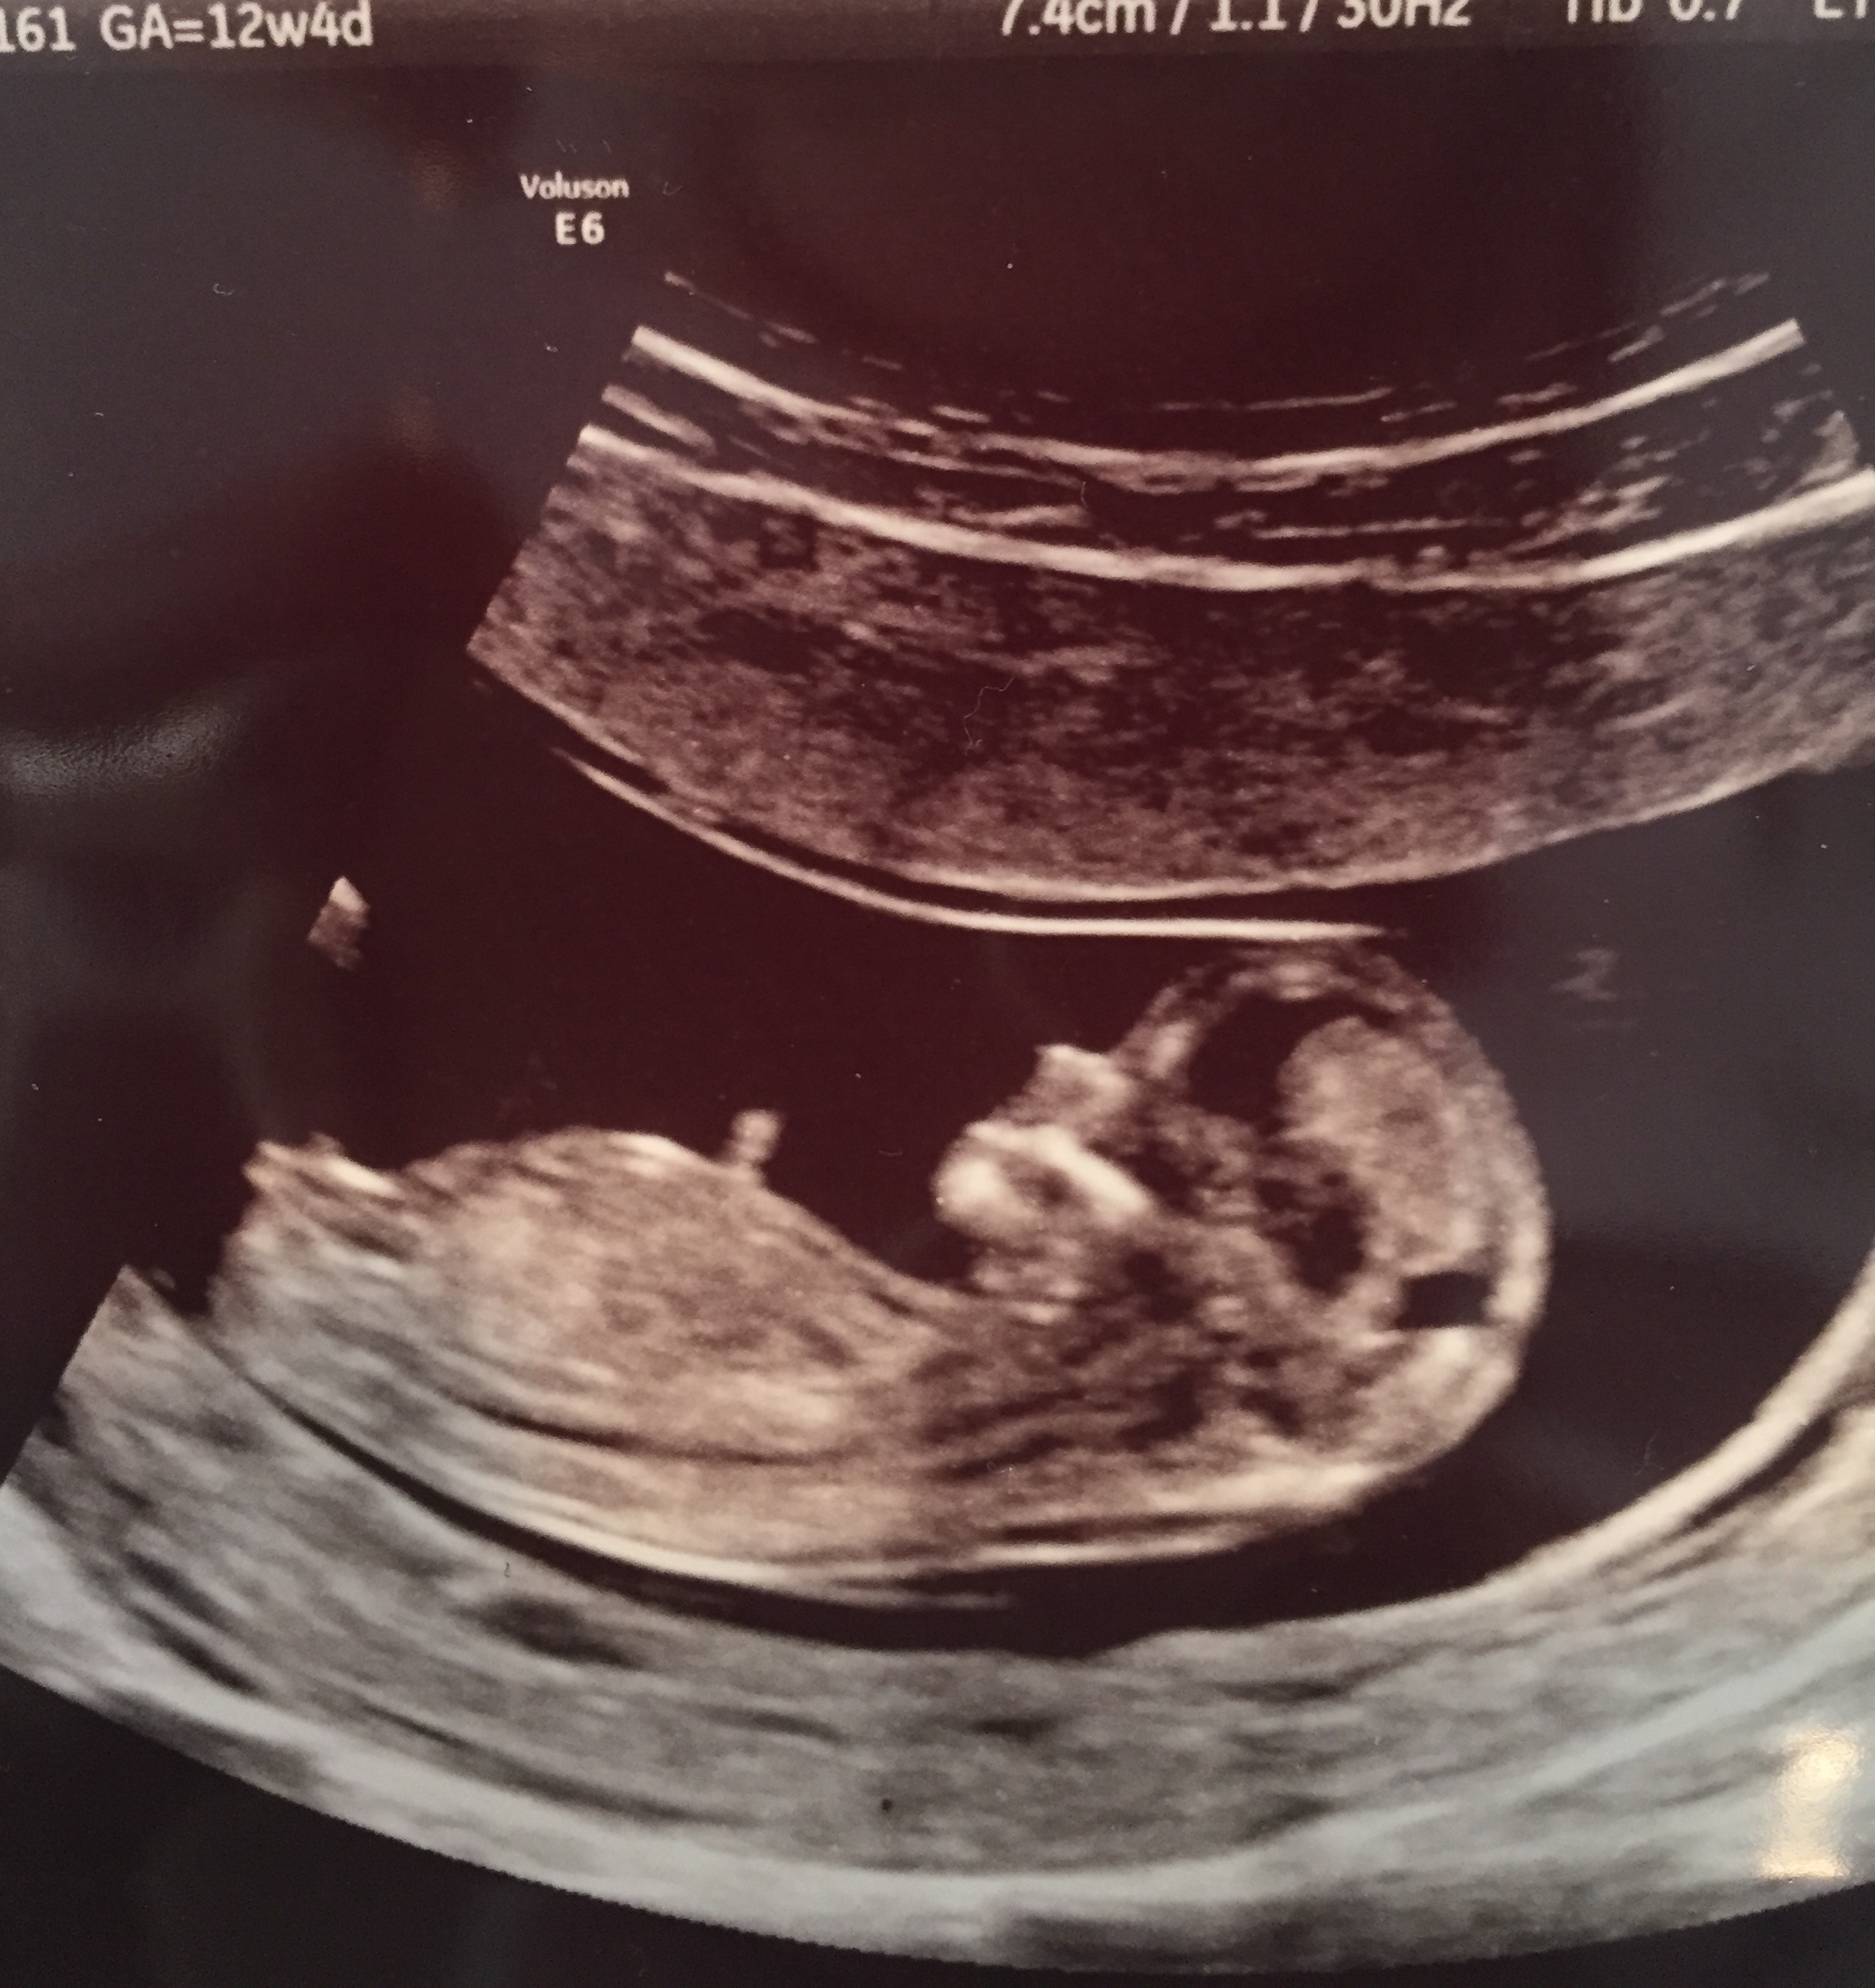

12 weeks, 4 days. Guesses on girl or boy? Thank you!!Attachment 22903